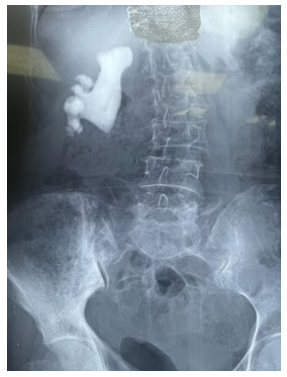

In recent decades, there has been a significant shift in the surgical management of renal lithiasis. Urologists face a therapeutic hurdle when treating coralliform calculi. The use of open or laparoscopic surgery has drastically decreased as a result of advancements in extracorporeal lithotripsy (ESWL), ureterorenoscopy (URS), and percutaneous nephrolithotomy (PCNL) in terms of minimally invasive access (flexible URS, combined techniques), energy (sonotrodes, and various types of laser), and technique. [1,2,3]. We report the case of a 70 years old female patient, who consulted for a simple right renal colic, the patient underwent an KUB radiography which found a calcium-toned opacity (Figure 1). We completed with and CT scan showing a dilatation du to complex lithiasis (89x23x33mm 1141 HU) (Figure 2).

Figure 1: KUB radiography showing and calcium toned stones